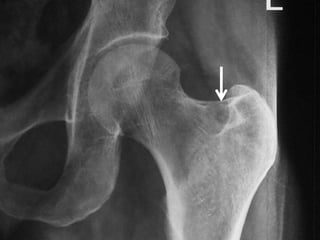

• Any bone can be involved,

• There is a predilection for the lower extremity,

with half the cases involving the femur or

tibia.

• The tumor may be found in cortical or

cancellous bone, producing a distinct x-ray

appearance of cortical sclerosis.

• 5% of tumors are subperiosteal.

• Routine roentgenograms often are diagnostic,

but bone scans or CT are often required to

localize the lesion accurately.

Osteoid Osteoma

• CT may detect the nidus, whereas

roentgenograms show only sclerosis.

Osteoid Osteoma • Anybone can be involved, • There is a predilection for the lower extremity, with half the cases involving the femur or tibia. • The tumor may be found in cortical or cancellous bone, producing a distinct x-ray appearance of cortical sclerosis. • 5% of tumors are subperiosteal.